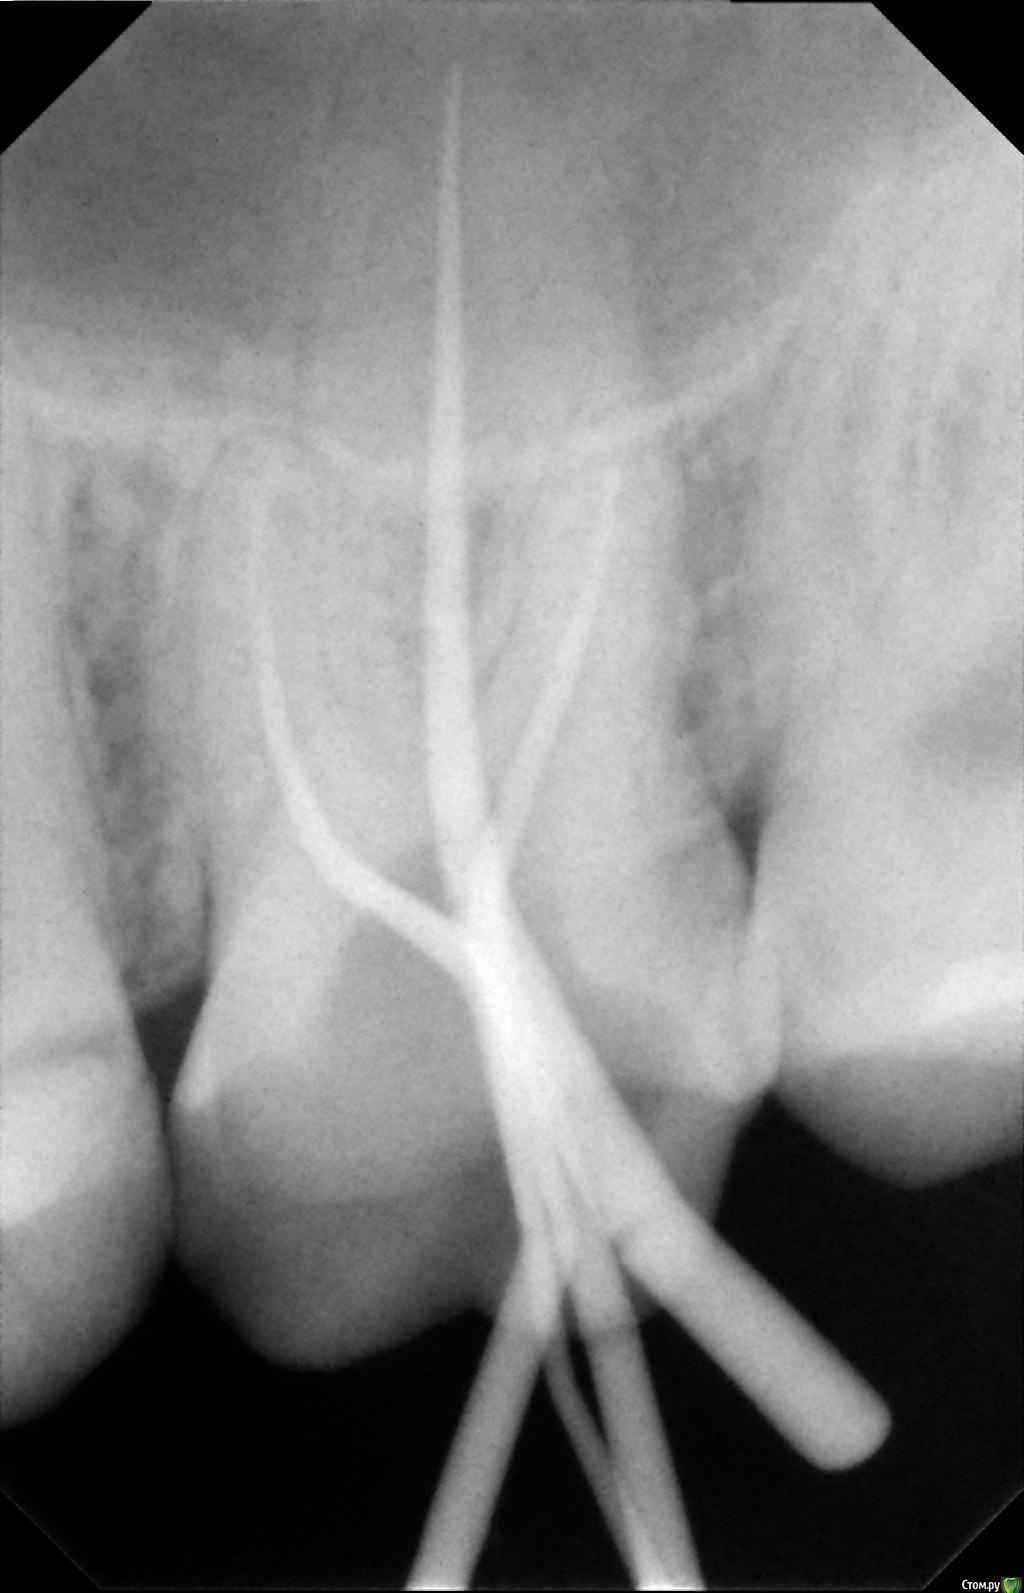

К сообщению прикреплены фотографии процесса лечения 26-го зуба.

После пломбировки каналов, я решил пойти ставить коронку в другую клинику, но там мне сказали, что не дают гарантию на этот зуб, поскольку каналы не долечены, и что я могу обратиться по гарантии в первую клинику. Но в первой клинике мне сказали, что все долечено. Хочу узнать мнение специалистов по этому поводу. Должен ли канал очищаться и пломбироваться до самой границы корня? Видно ли, что зуб не долечен по этим снимкам?

Так же в первой клинике в процессе лечения мне говорили, что у меня в зубе 5 каналов. Из-за этого цена лечения должна была быть еще дороже, но сказали, что мне оказали благосклонность и вылечили пятый канал бесплатно. В другой клинике мне сказали, что информация про 5-й канал - это ложь.